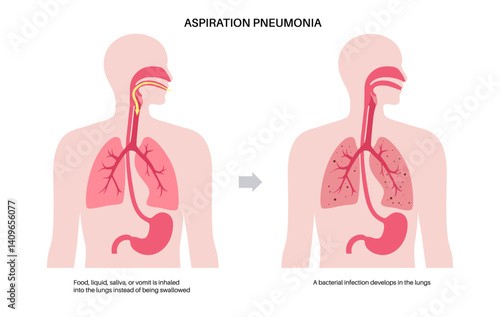

Aspiration - Posters, Wall Art, Canvas Prints